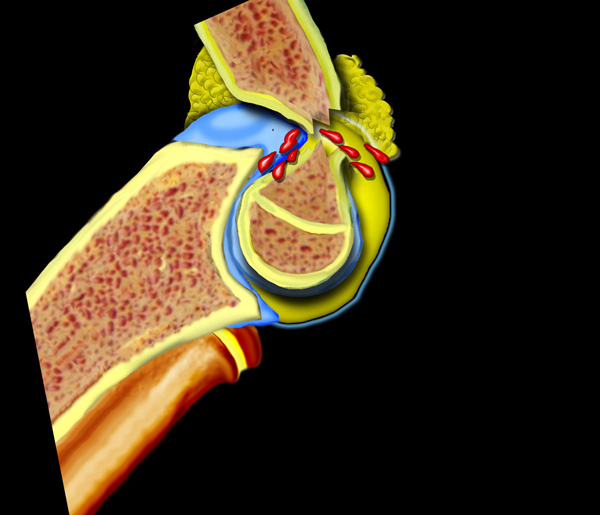

Thông thường trên phim chụp nghiêng của khớp khuỷu gấp 90°, có thể thấy một đệm mỡ ở phía trước của khớp.

Đây là lớp mỡ bình thường nằm trong bao khớp.

Ở phía sau không thấy đệm mỡ vì lớp mỡ phía sau nằm sâu trong hố gian lồi cầu.

Dấu hiệu đệm mỡ dương tính

Sự căng phồng của khớp sẽ khiến đệm mỡ phía trước bị nâng lên và đệm mỡ phía sau trở nên hiện rõ.

Vùng thấu quang phía trước bị nâng cao hoặc vùng thấu quang phía sau hiện rõ trên phim X-quang thẳng nghiêm thực sự của khuỷu tay gấp 90° được mô tả là dấu hiệu đệm mỡ dương tính (hình).

Tràn máu khớp gây ra sự dịch chuyển lên trên của đệm mỡ trước và sự dịch chuyển ra sau của đệm mỡ sau.